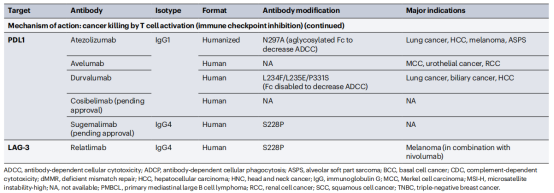

人表皮生长因子受体2(HER2)特异性抗体结合不同的HER2表位。HER2胞外域(ECD)与Trastuzumab和Pertuzumab片段抗原结合(Fab)结构域结合,这种复合物结构指导了双特异性抗体zanidatamab的设计。通过这种结构分析技术,可以用来了解Rituximab的治疗机制,通过结构分析,发现CD20会形成一个二聚体,每个CD20分子与一个Rituximab的Fab结合。Rituximab通过交联CD20二聚体形成大的超分子复合物来促进CD20的聚集。